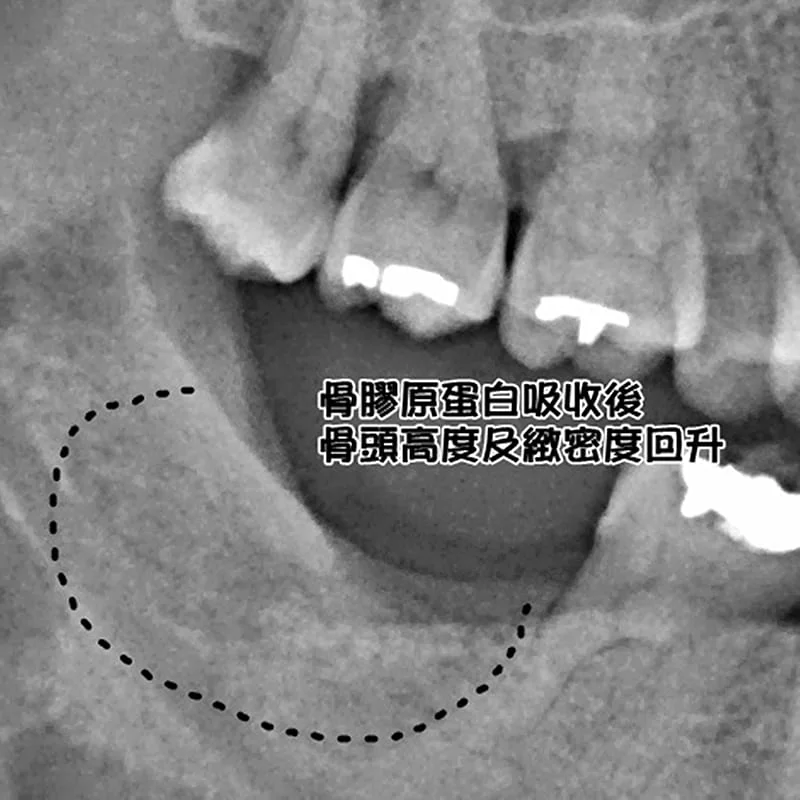

局部麻醉下,進行牙齒拔除,並填置骨膠原蛋白後,縫合,等一週牙肉癒合拆線,三個月後,回診檢查骨頭狀況。

( 治療後 )

( 治療後:骨膠原蛋白轉換成正常骨頭,X光片上呈顯骨頭高度及緻密度回升 )

為什麼需要用骨膠原蛋白? 骨膠原蛋白容易置入拔牙齒槽窩洞內,海綿狀的彈性能充分填入傷口中,傷口約1-2週即可癒合,當拔除牙齒時,傷口部位置入骨膠原蛋白後,止血、減痛、加速傷口癒合效果立即顯現,另一方面促進本身齒槽骨再生,三個月後骨膠原蛋白被吸收取代,牙周結實美觀,無論是維持骨頭的外觀,或是進一步植牙都沒問題,基於這些優點骨膠原蛋白確實是個不錯的選擇。